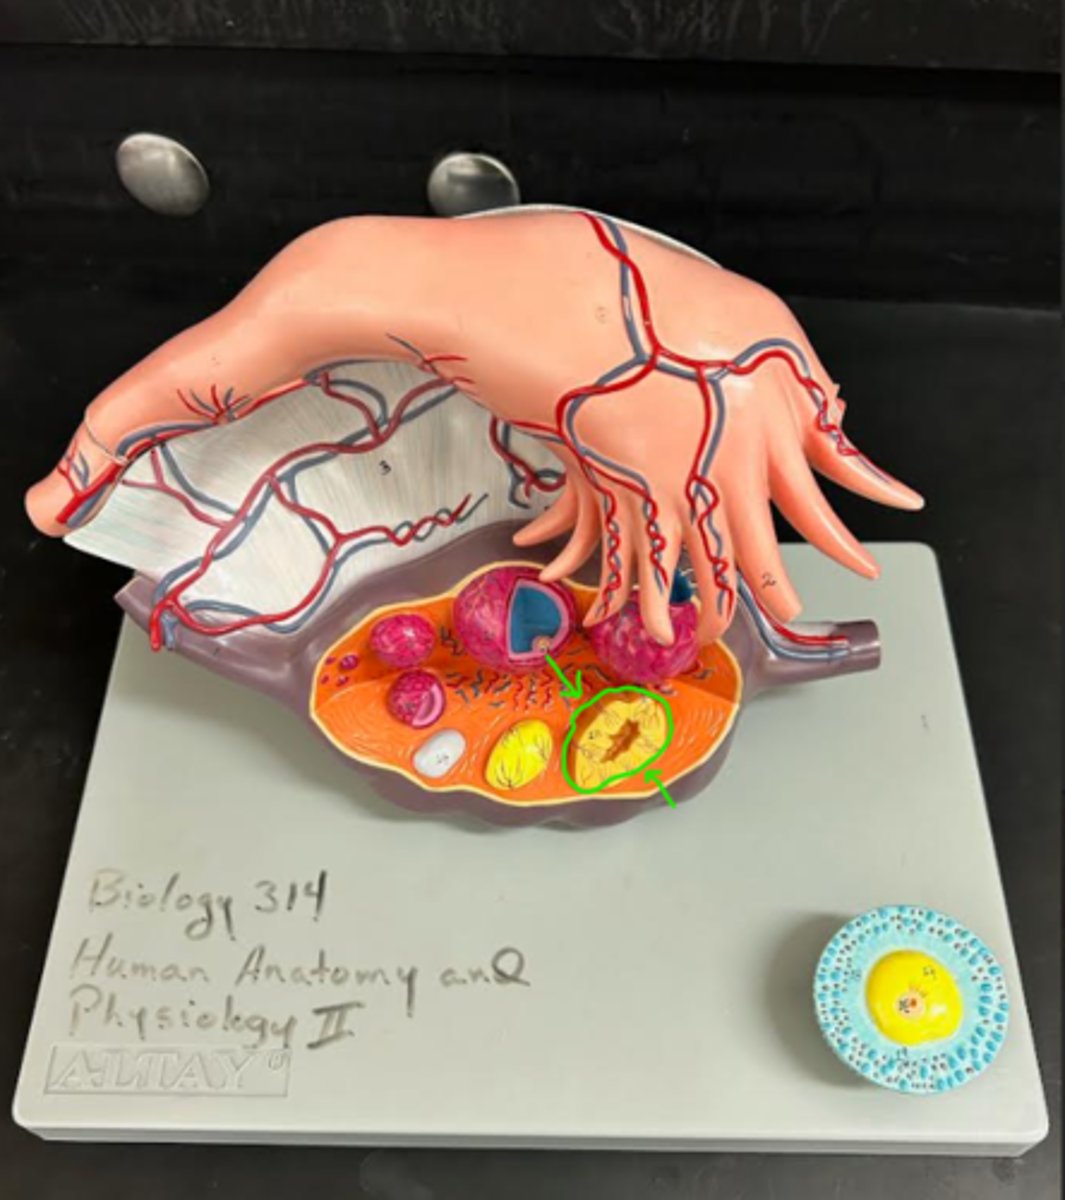

ovary

1

primordial follicle

a

secondary follicle

b

ruptured follicle

c

granulosa cells

d

corpus luteum

e

secondary oocyte

g

ovum

h

zygote

i

blastocyst

l

endometrium

m

corpus albicans

f

uterus

3

fallopian tube

2

umbilical cord

n

placenta

o

right ovary

1 (lt or rt)

infundibulum

2

ampulla

3

isthmus

4

fundus

5